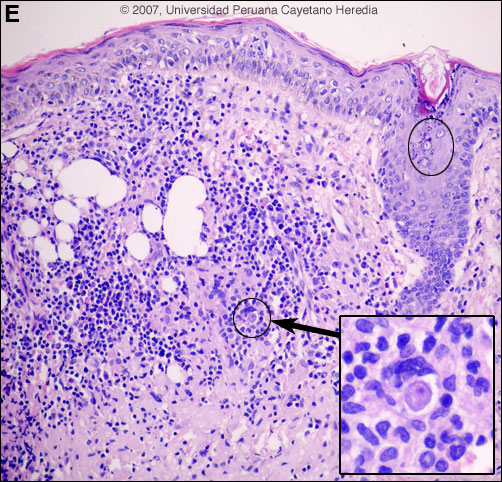

![]() Discussion: A skin biopsy of the lesion over the nose showed a dense immflamatory infiltrate of the dermis composed of lymphocytes, plasma cells and multinucleated cells with granulomas. There are multiple trophozoites of a free-living amoeba [Image E, ovals]. Note the small nucleus eccentrically located and the vacuolated cytoplasm [Image E, magnification]. Definitive identification of Balamuthia requires culture or specific immunostaining, and successful use of PCR has been reported. However, other species of free-living amoeba are not known to occur in Perú. Around 100 cases of Balamuthia mandrillaris have been reported since the organism’s initial description in 1990 [Clin Infect Dis. 1997 Dec;25(6):1354-8]. Half or so have been in the USA, mostly in immunocompromised patients. Cases have also occurred in Canada, Mexico, Australia, Argentina, Brazil, Mexico, Thailand, Japan, the Czech Republic, Portugal, and England. A significant number of the published cases from the United States have occurred in persons of Hispanic ethnicity. Additional reports have come from Canada, Japan, Australia, Thailand, and Eastern Europe, as well as from throughout Latin America. We have seen over 50 cases at our institution and, like most Latin American cases, the patient is not immunocompromised. Unlike Acanthamoeba and Naegleria species, which are more familiar to clinicians and known to occur in brackish ponds and creeks, an ecologic niche in nature has not been definitively found for Balamuthia. Our patients have come from throughout rural areas of Perú, and usually, but not always, have a history of swimming in potentially contaminated fresh water. Entry of water into the nasal mucosa and the olfactory nerve endings is thought to occur with Acanthamoeba and Naegleria. Naegleria infection causes an acute necrotizing and suppurative meningoencephalitis, an aggressive disease that is generally fatal in days. Acanthamoeba cause a sub-acute granulomatis encephalitis with a more prolonged but ultimately fatal course. Occasionally patients with Acanthamoeba have a skin lesion usually described as a chronic ulcer. Acanthamoeba, unlike Balamuthia, has been associated also with amoebic keratitis, a painful sight-threatening disease of the eye. In Balamuthia infection the disease may follow a prolonged course, but most frequently has a fatal outcome. Almost all cases have an initial skin lesion, and this lesion precedes the inevitable CNS disease (granulomatous amebic encephalitis) by weeks or months. Patients have ranged from 5 to 65 years of age with 50% under age 15. The typical skin lesion is a single painless plaque up to several centimeters in diameter; a few patients have had 2 to 3 lesions. Color may be skin tone, dark red, or slightly violaceous. Sensation is preserved. Location is usually on the central face but occasionally on trunk or extremities. For facial lesions the differential diagnosis may include tuberculosis, mucocutaneous leishmaniasis, leprosy, sporotrichosis, paracoccidioidomycosis, rhinoscleroma, or mucormycosis. Sarcoid, discoid lupus, and Wegener's can also be considered. Histologically, granulomatous inflammation with lymphocytes, histiocytes, plasma cells, as well as giant cells, is characteristic. Amoebic trophozoites are often scanty and multiple sections need to be examined. Some foci of vasculitis may be present. CNS involvement manifests with heachache, photophobia, seizures that progress to lethargy, sensorimotor deficit, coma and death. The CNS lesion is a progressive hemorrhagic necrosis with large numbers of amoebic trophozoites and cysts invading vascular sub-adventitial areas of arteries, veins, and capillaries, leading to perivasculitis and cerebral infarcts [Hum Pathol. 1999 Mar;30(3):269-73]. No therapy has been shown to be highly effective in curing Balamuthia infection. With IV amphotericin B or pentamidine, an initial and apparently favorable response or disappearance of cutaneous lesions still does not halt the eventual appearance of CNS disease. Similarly, in our hands, multi-drug combination therapy with agents such as albendazole, itraconazole, or fluconazole have still resulted in eventual appearance or progression of CNS disease. In our hands there have been 4 survivors out of 10 patients treated with aggressive combination therapy followed by 6-12 months of albendazole maintenance. One or two case reports from other centers have reported success with regimens that have also included sulfadiazine, macrolides and phenothiazines. The current patient was started on fluconazole 400 mg/d, albendazole (800 mg/d) and amphotericin B 1.0 mg/kg/d. He developed gait abnormalities and increased intracranial pressure on Day 3 of hospitalization and died 1 week later.